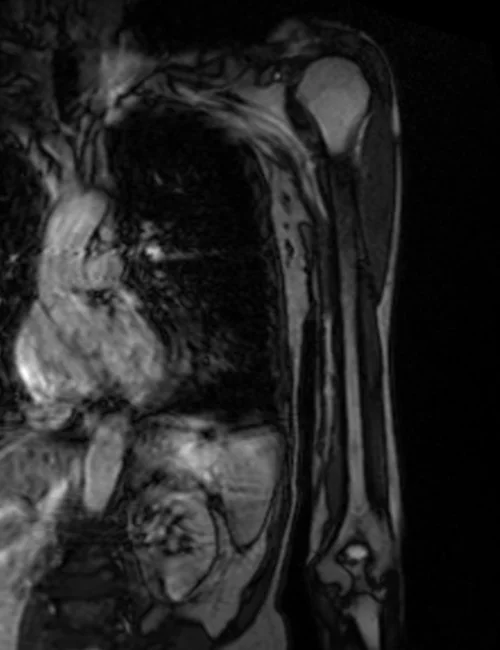

mra upper arm loc 1 - MRI